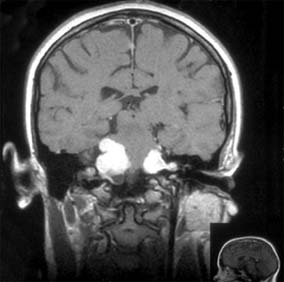

During an acute episode of optic neuritis, MRI shows gadolinium enhancement, increased signal on short tau inversion recovery (STIR) sequences, and sometimes swelling of the affected nerve. Brain MRI will show lesions consistent with demyelination in as many as 25% of patients with isolated optic neuritis (Figure 14-10). This does not establish a diagnosis of multiple sclerosis, though it does indicate a significantly increased risk of subsequent development of clinically definite multiple sclerosis. The value of steroid treatment in delaying the development of multiple sclerosis is greater in patients with abnormal brain MRI at presentation. Thus, brain MRI may be indicated in isolated optic neuritis if more precise information is wanted about the risk of multiple sclerosis and the value of systemic steroid treatment.

Figure 14-10

Figure 14-10: Cerebral hemisphere white matter lesions on MRI associated with acute demyelinative optic neuritis.